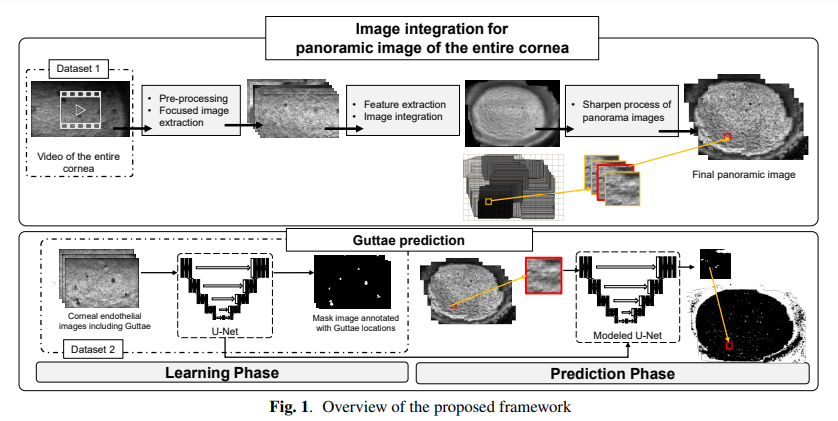

▌Generating corneal panoramic images from contact specular microscope images

作者单位:同志社大学(日本)

论文链接:https://arxiv.org/abs/2301.02388

本研究提出了一个框架,从使用接触镜显微镜拍摄的视频中自动生成整个角膜图像。从视频中提取了相对集中的图像,并进行了全景合成。如果能生成整幅图像,就有可能从图像中检测出guttae并检查其存在的程度。系统使用U-Net的监督学习模型来检测。